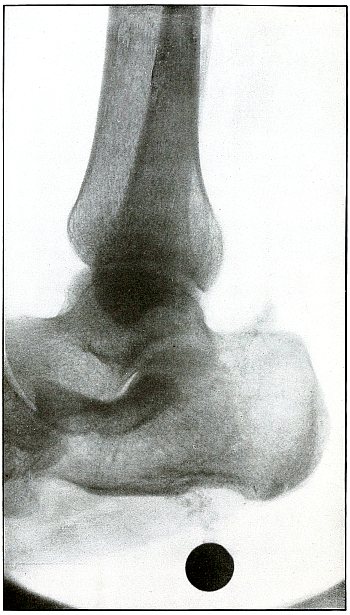

Gunshot fracture, ankle |

154 |

| 73. |

Gunshot wound, heel |

156 |

| 74. |

Gunshot wound, heel |

158 |